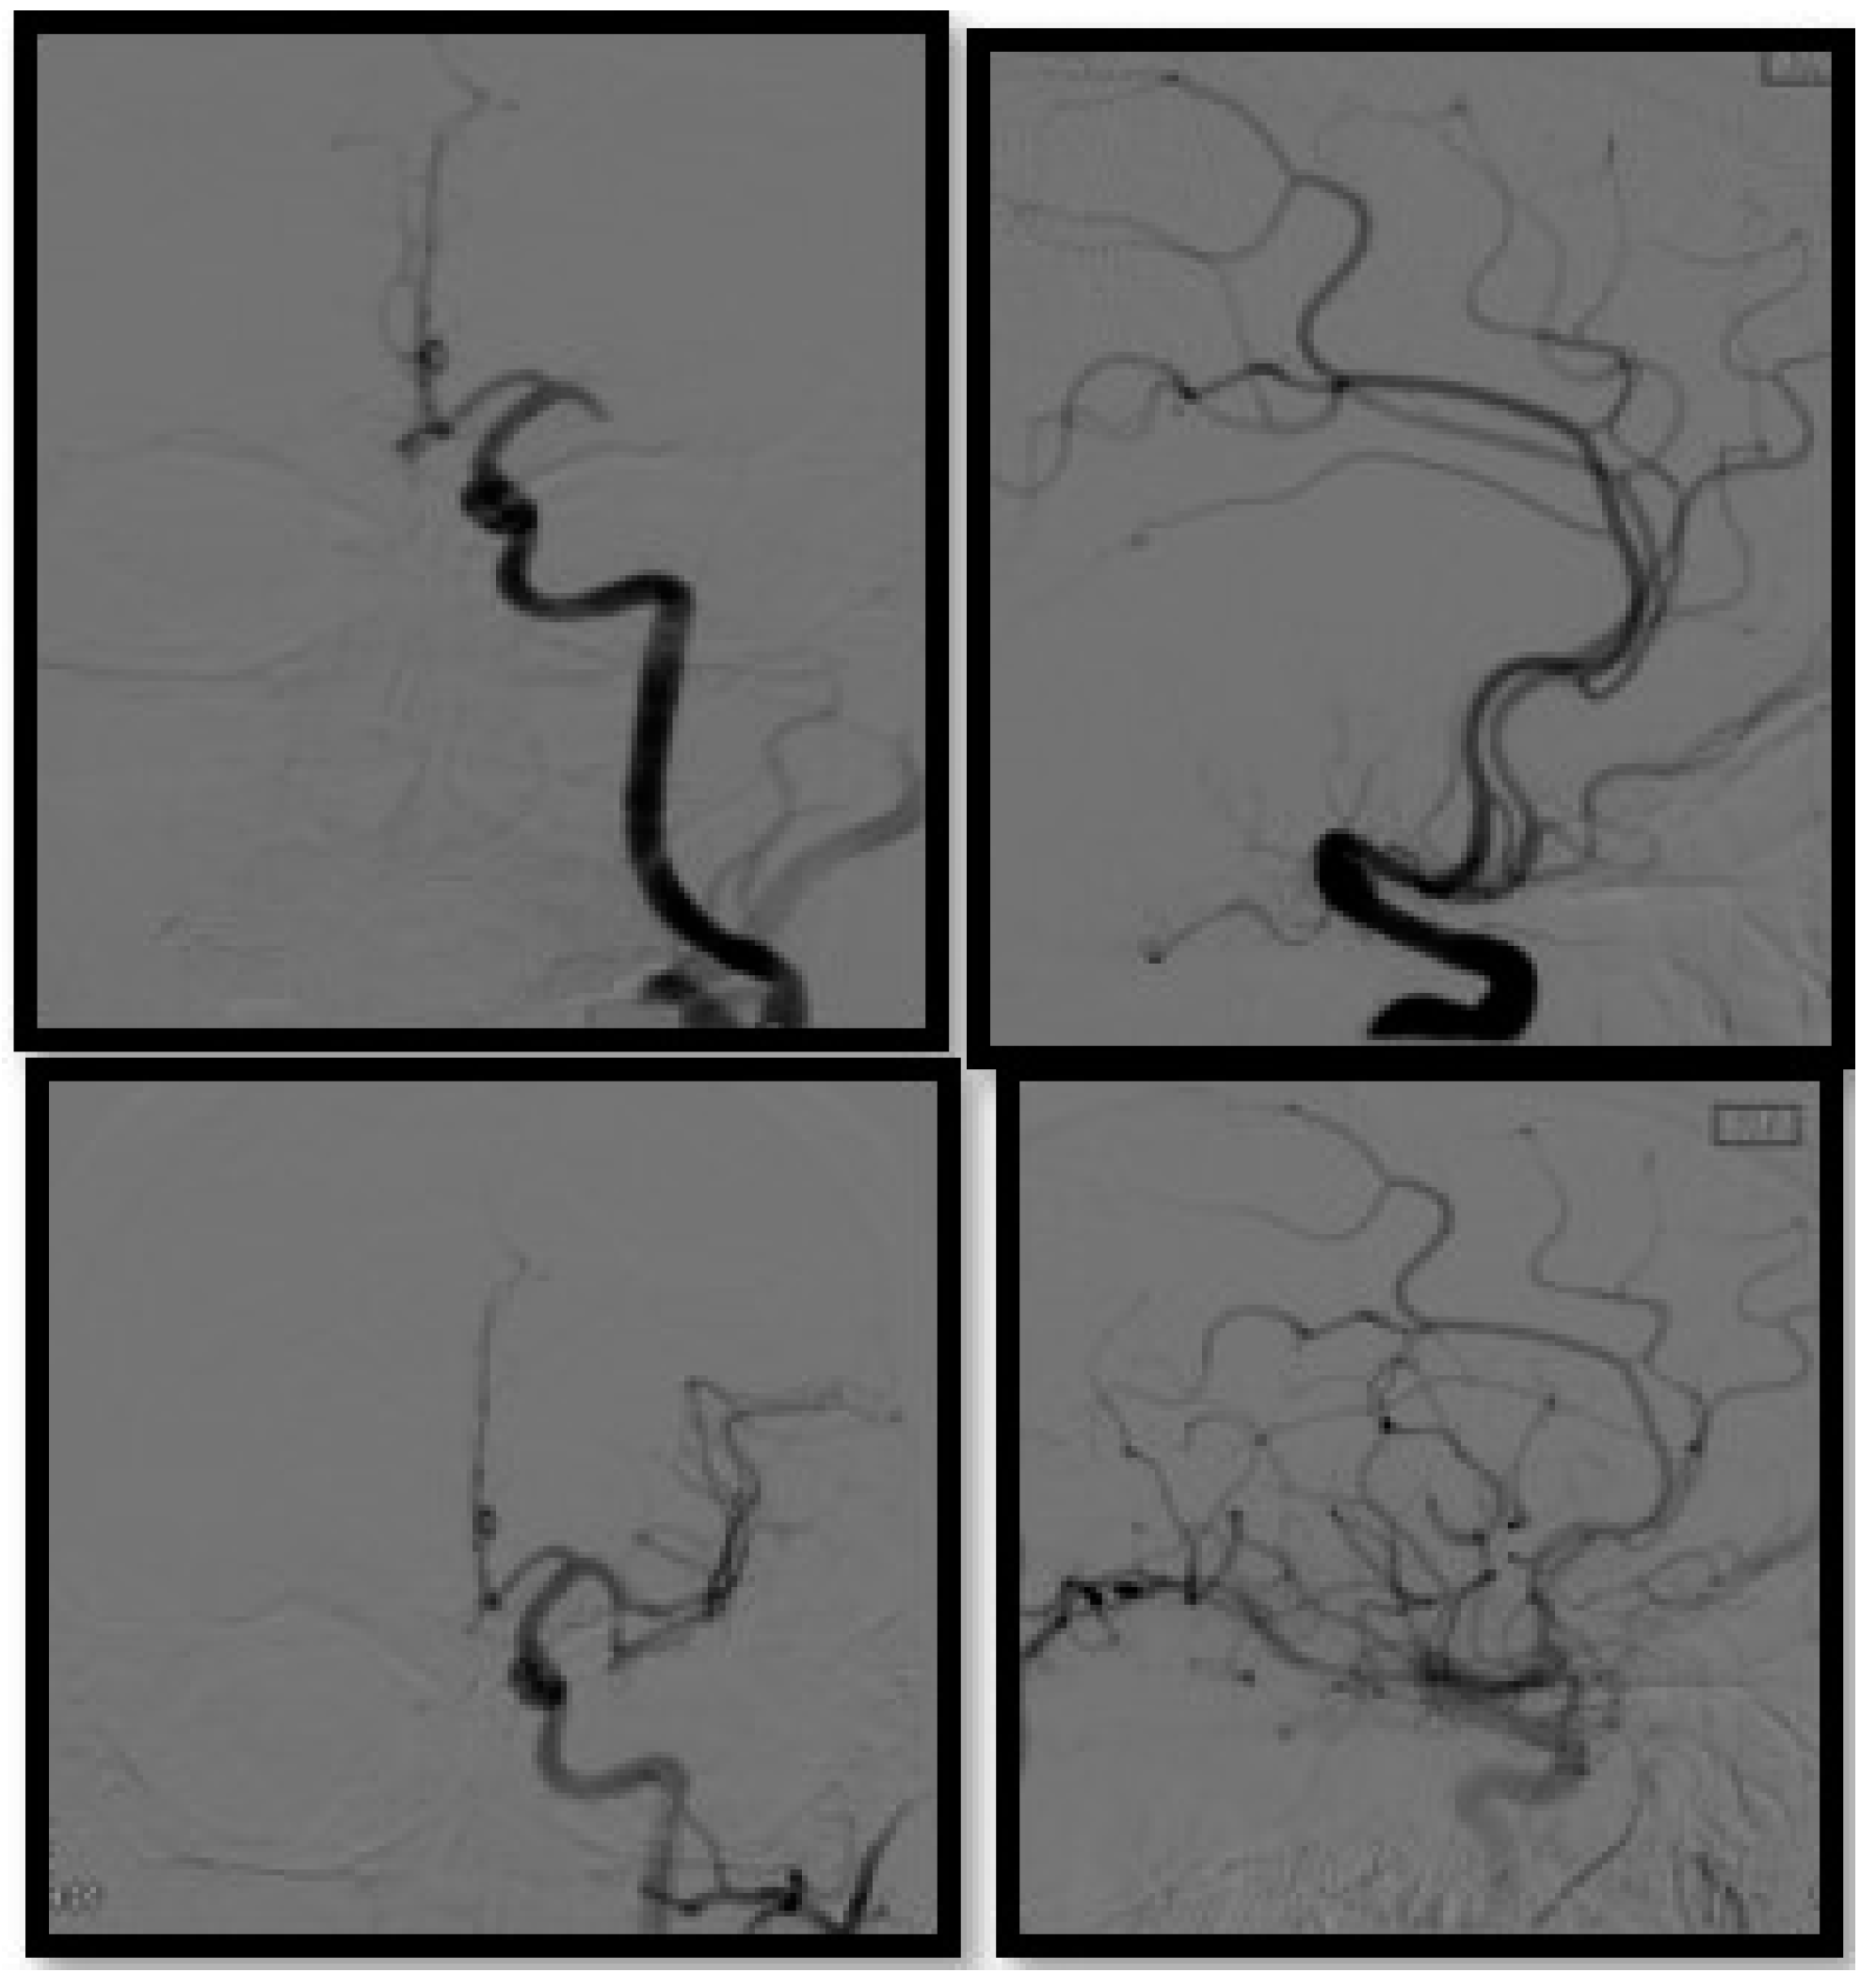

- Artico, M.; Spoletini, M.; Fumagalli, L.; Biagioni, F.; Ryskalin, L.; Fornai, F.; Salvati, M.; Frati, A.; Pastore, F.S.; Taurone, S. Egas Moniz: 90 Years (1927–2017) from Cerebral Angiography. Front. Neuroanat. 2017, 11, 81. [Google Scholar] [CrossRef] [Green Version]

- Smith, W.S.; Furlan, A.J. Brief History of Endovascular Acute Ischemic Stroke Treatment. Stroke 2016, 47, e23–e26. [Google Scholar] [CrossRef] [Green Version]

- Boyle, K.; Joundi, R.A.; Aviv, R.I. An historical and contemporary review of endovascular therapy for acute ischemic stroke. Neurovascular Imaging 2017, 3, 1. [Google Scholar] [CrossRef]